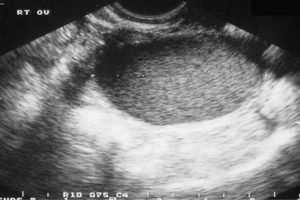

Diplomados en Ultrasonografía